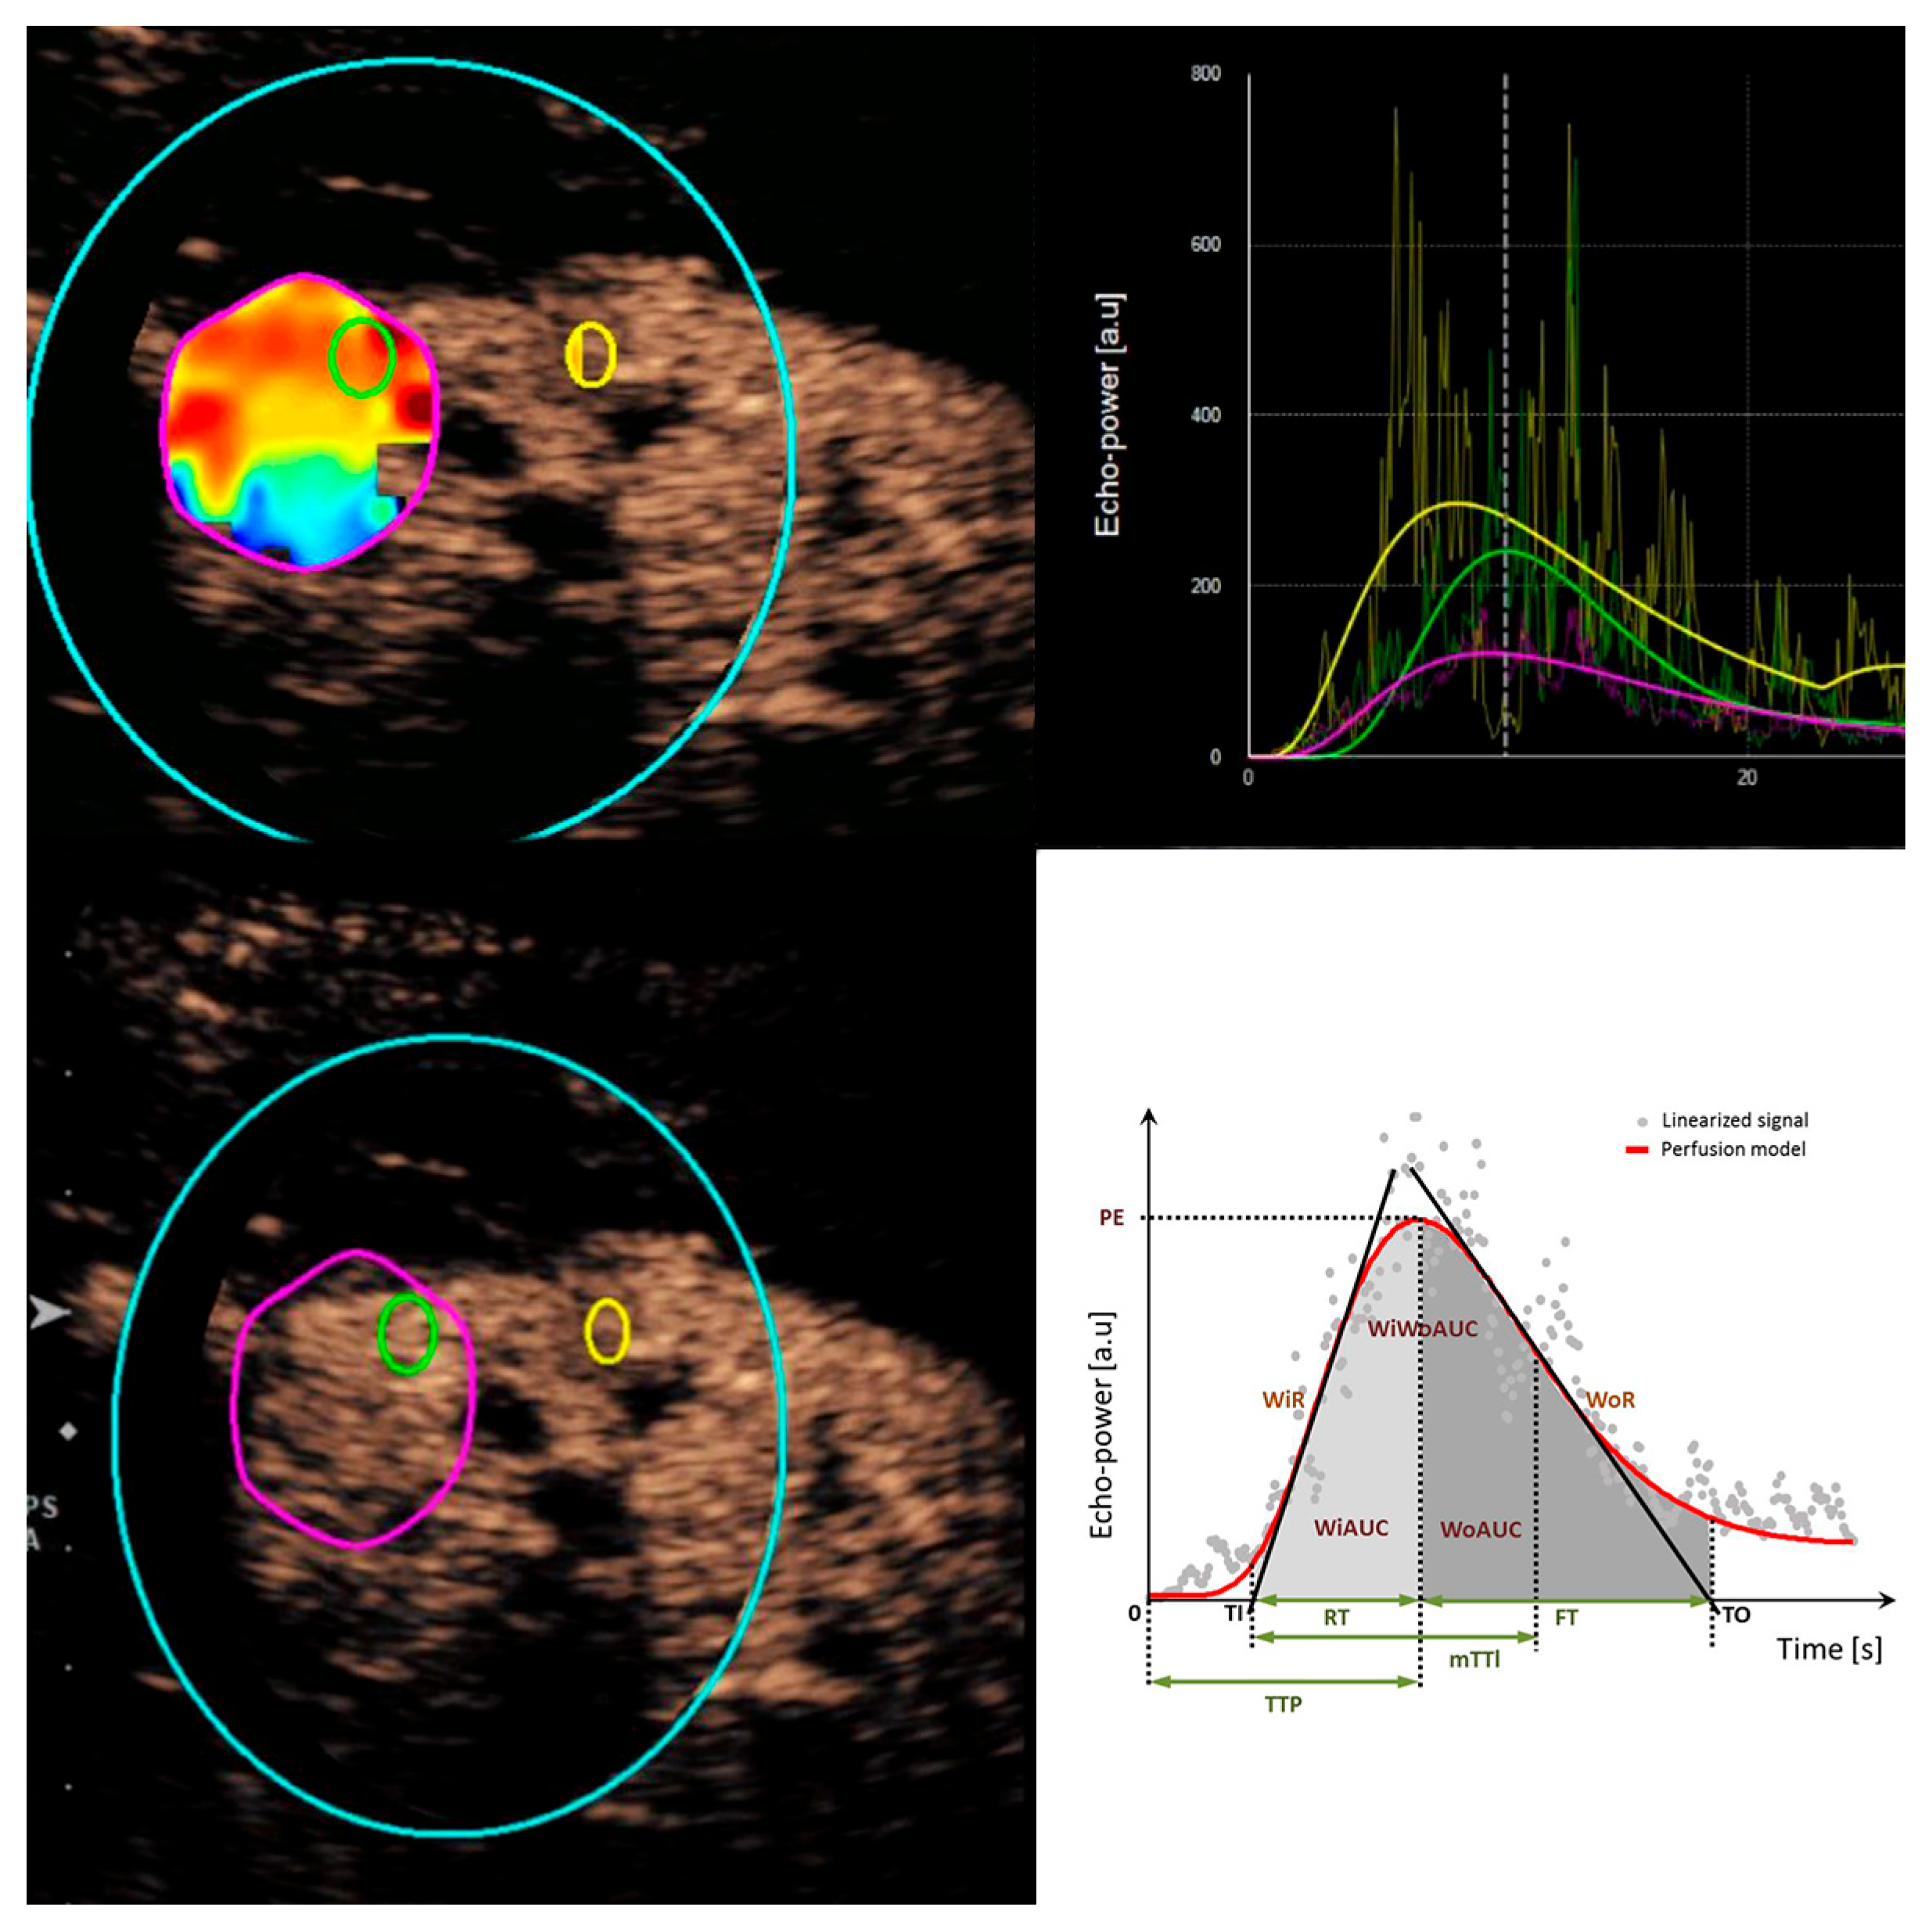

2.2. Image Acquisition and Analysis